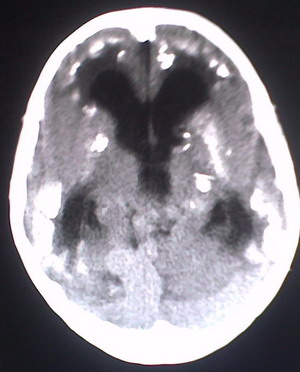

以下是引用jiajie在2009-2-3 20:02:00的发言:[br]脑室周围白质区可见大量斑片状钙化,部分融合成带状,双侧侧脑室及第三脑室扩大。[br]考虑弓形体原虫感染。(先天性宫内感染、torch综合症)

以下是引用lkc8963在2009-2-3 21:15:00的发言:[br]临床眼睑可见静脉扩张,ct双侧眼上静脉亦示扩张,颅内钙化以皮层\\软脑膜为主而不是位于白质和室管膜,再加上静脉窦异常,还是应该考虑静脉血管瘤病,可能为较复杂的血管畸形.

以下是引用卜一在2009-2-4 9:21:00的发言:[br]sturge-weber综合征:面部三叉神经分布区的毛细血管性或海绵状血管瘤以及同侧枕、顶或额叶软脑膜的血管瘤(以静脉性为主)。脑皮质,特别是第二三层,毛细血管可有增厚和钙化。局部发生层状坏死、神经细胞脱失、萎缩、胶质细胞增生及钙盐沉着。可根据面部典型分布的特征性皮痣作出诊断。头颅ct:发现面部血管瘤同侧的脑内病理钙化影,呈双层线条波浪形、脑回形或树枝形。本例支持:sturge-weber综合征![br]